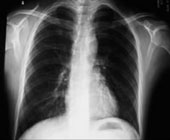

其他辅助检查:根据临床表现选做心电图、B超、脑CT等。